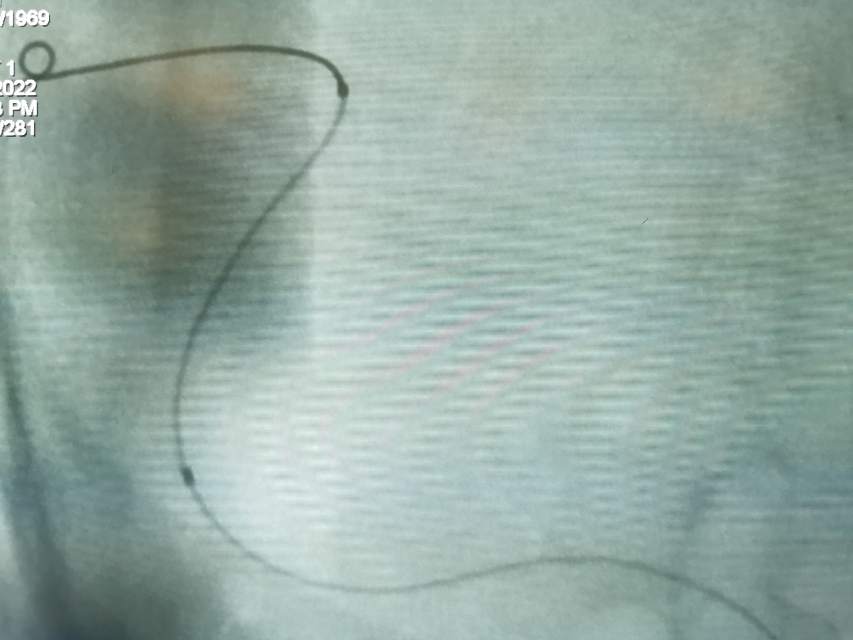

福建中年女性,近期在外查出“颅内动脉瘤”,经推荐转来我院诊治。患者的颈内动脉通路迂曲,动脉瘤也位置奇特,解剖复杂,动脉瘤远近段的血管弯弯绕绕,重重叠叠,眼花缭乱,难以兼顾找到最佳位置。最终克服困难,将“基底型”动脉瘤改变为“侧壁型”动脉瘤,顺利给予治疗……